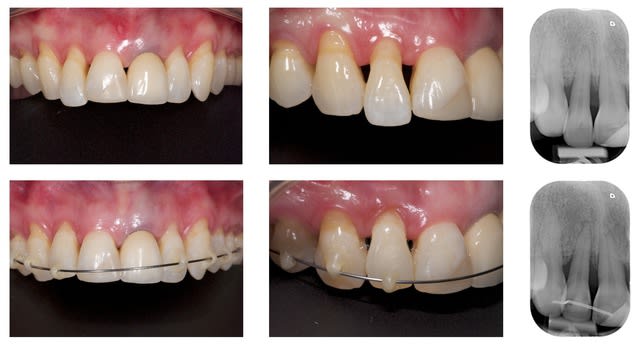

Le support paro est stable depuis 3 ans et la maintenance parfaite. je pense ici qu'un traitement ortho serait une bonne solution. j'ai déjà effectué un traitement similaire sur une 12 égressé ( confère photo ci-joint) et même si comme certain l'ont décrit, on a quelques aléas a cette méthode, ca vaut le coup d'essayer.

Merci dancha d'intervenir, j'avoue que j’espérerai bien que ce cas te face sortir de ta tanière et tes conseils sur eugenol m'avaient bien aidé pour réaliser le traitement ci-dessous.

Pour l'articles sur l'ingression et traitement paro, c'est assez logique en fait, pour espérer faire rentrer la dent dans l'os il faut recréer le ligament desmondontal dans une zone ou il avait disparut. Donc faire un traitement de surface avec d'ingresser semble logique.

Mais la un traitement similaire a ce que vous avez déja fait semble parfaitement adapté.